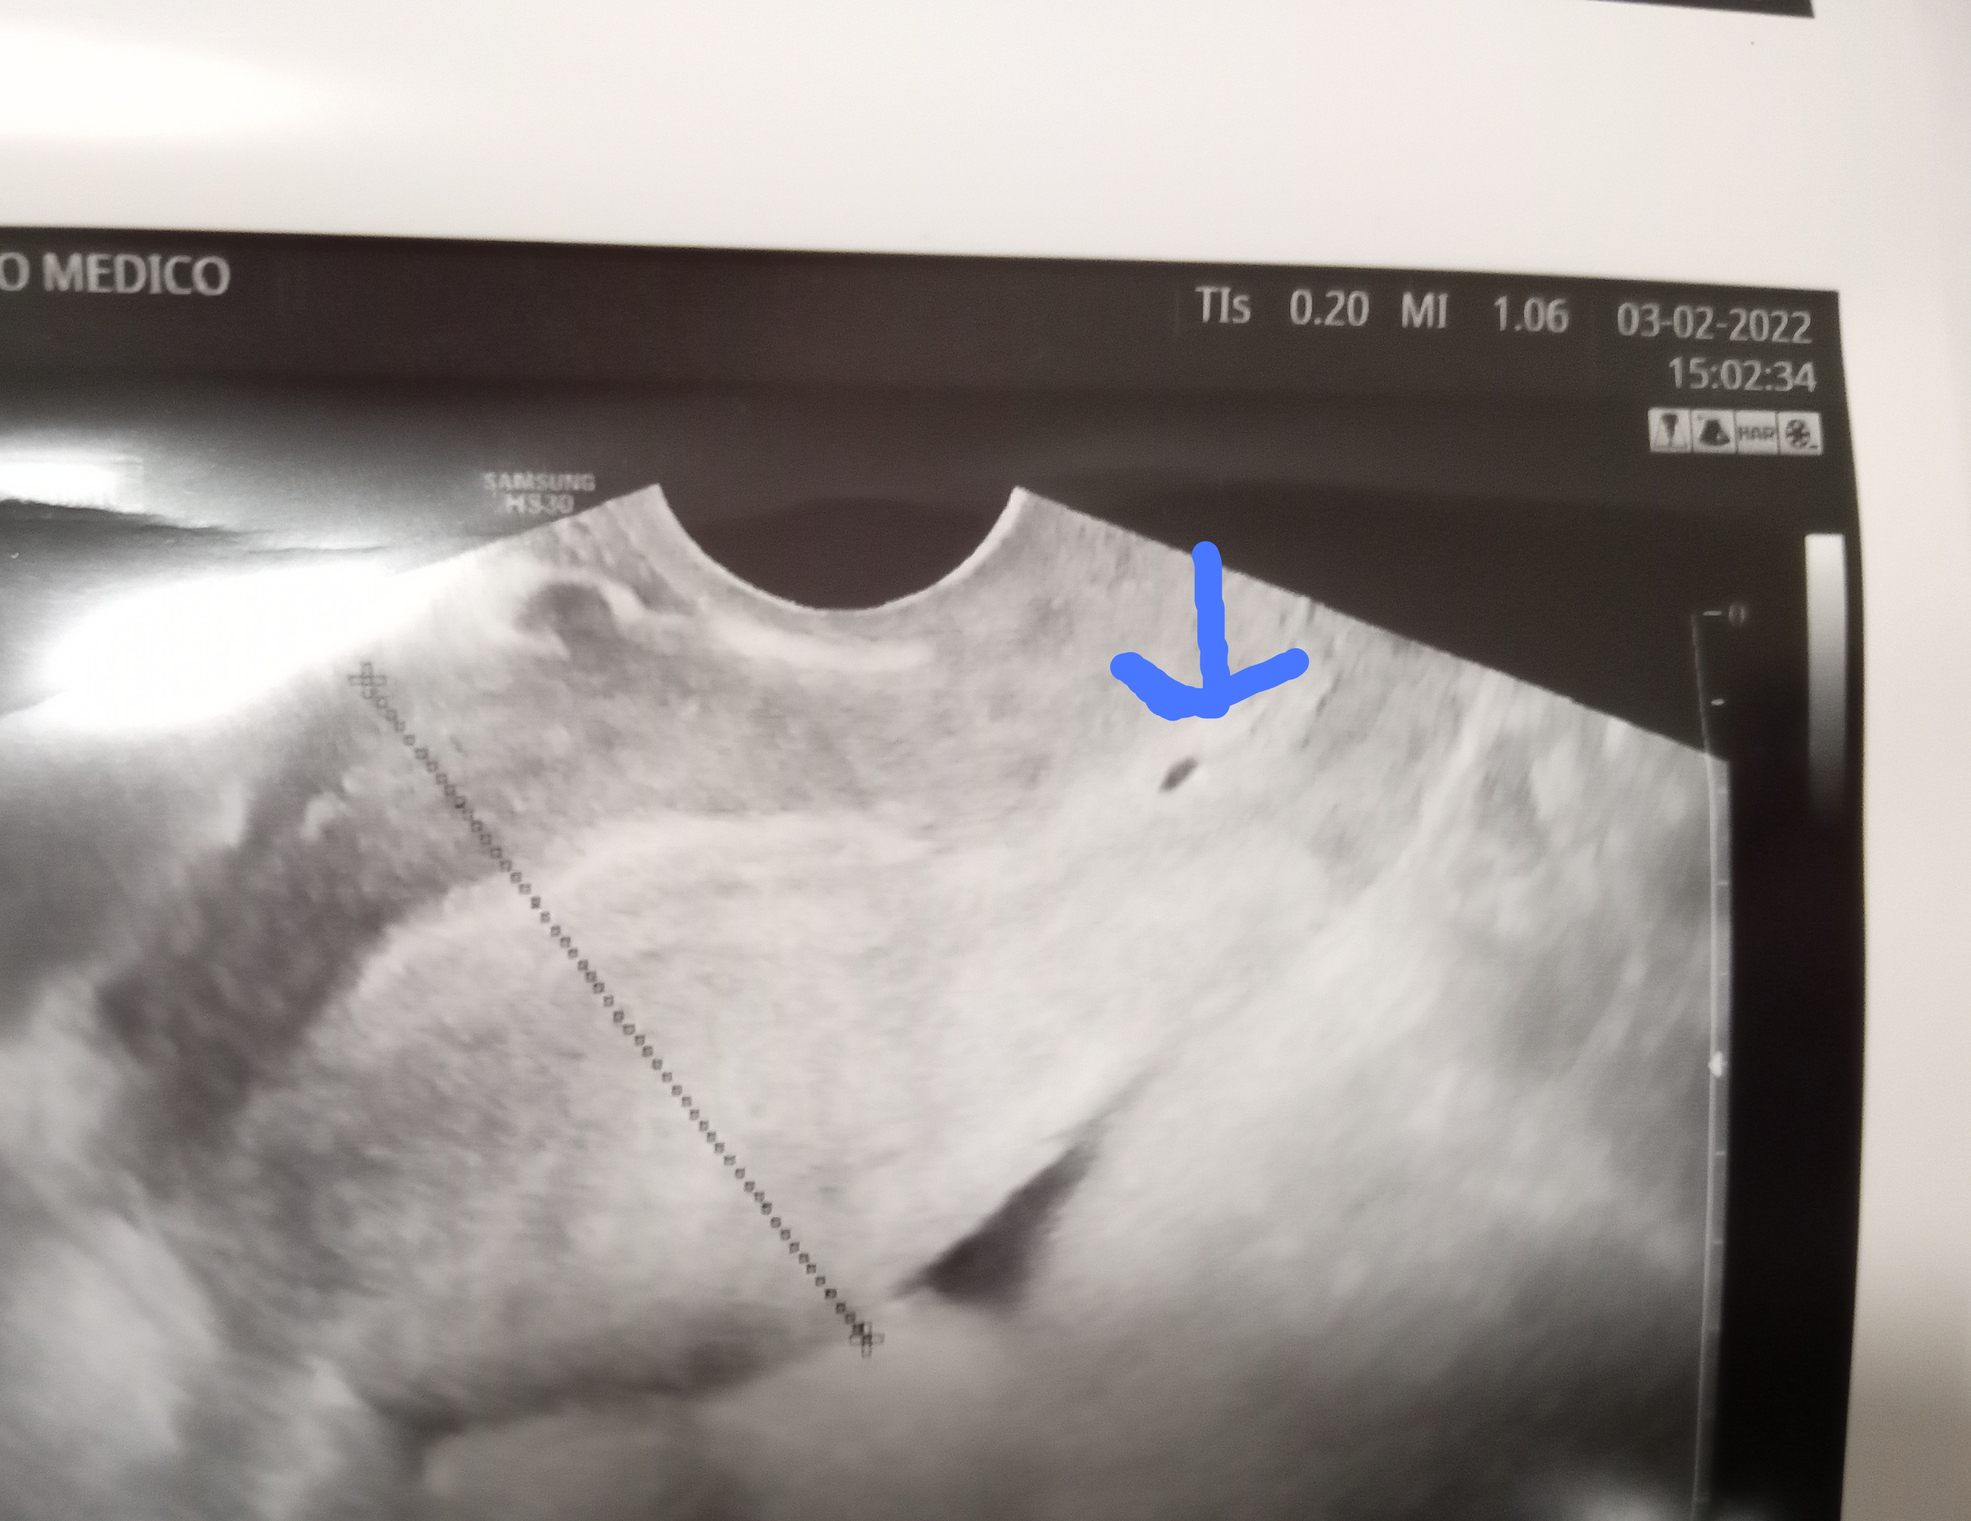

Hi I went for a check up..one week after having a lighter/irregular period and got this scan. Any opinions on what the black circle could be?

Yesterday I had some brown discharge and decided to go for a private ultrasound to check for abnormalities. (cysts ect) If I am pregnant this puts me at 5 weeks 5 days.

• @meggyme they said it's cervical mucus! Maybe at 5 weeks it will be missed